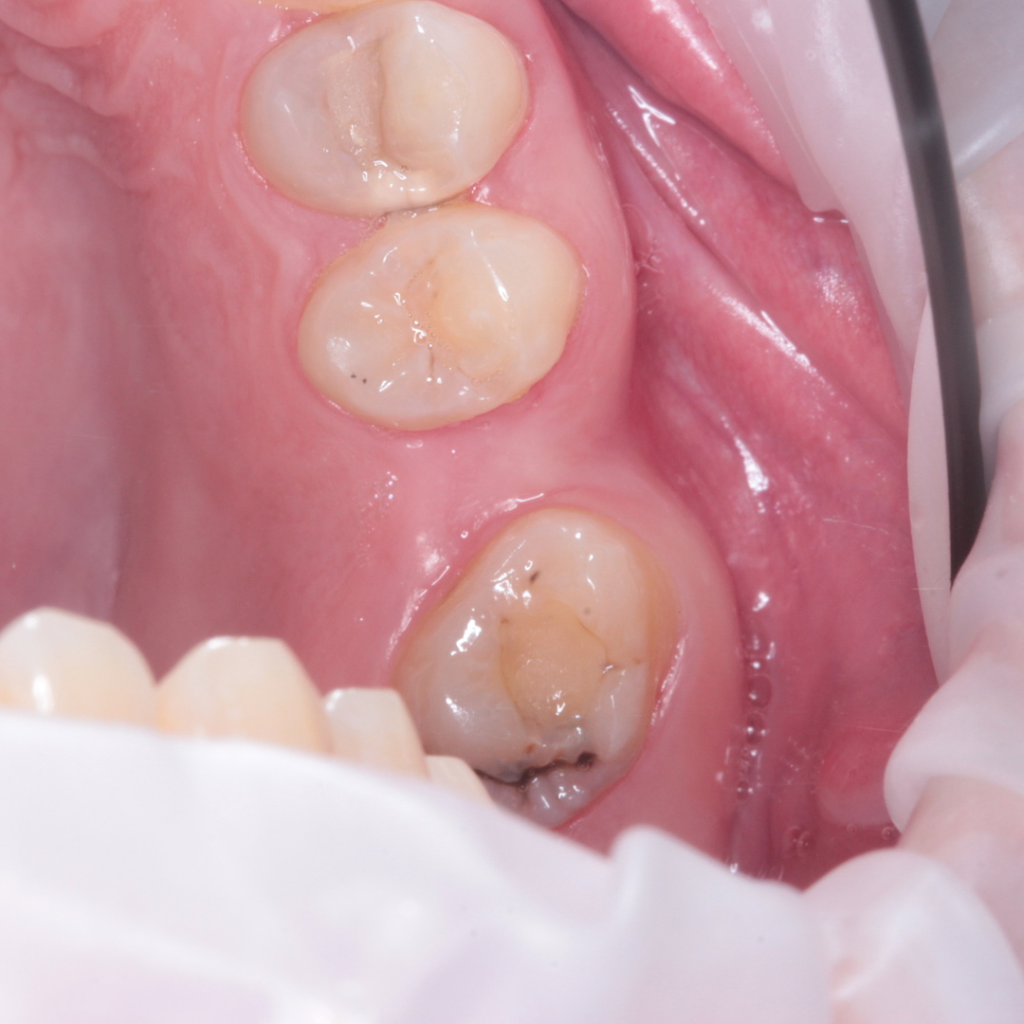

- Изготовление коронок в лаборатории R2Gate:

- временная коронка

- постоянная цельноциркониевая коронка

- керамическая вкладка на 17 зуб